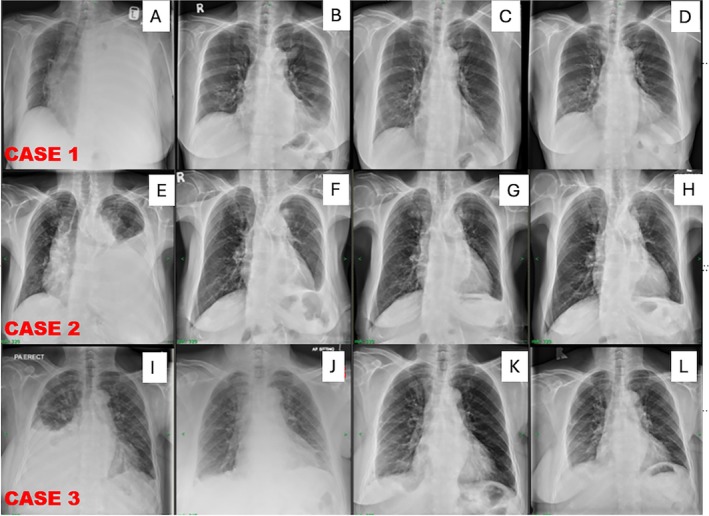

通过医学胸腔镜治疗恶性胸腔积液(MPE)是一项临床挑战,特别是在决定是否在同一情况下继续使用滑石粉时。由于肺再扩张的不确定性和胸膜切除术的潜在失败,这个决定往往很复杂。我们报道了3例癌症相关性MPE患者,他们接受了滑石粉粉末联合留置胸膜导管(IPC)的医学胸腔镜检查。这种联合入路是一种实用有效的策略,可以立即缓解症状,在可行的情况下促进早期胸膜联合,并在肺不扩张的情况下提供可靠的后备选择。双模技术强调了管理MPE的安全,灵活的途径,提高了手术信心和以患者为中心的结果。我们报告了3例MPE通过滑石粉和IPC联合成功实现胸膜固定术,并在随访中切除了IPC。

Management of malignant pleural effusion (MPE) via medical thoracoscopy presents a clinical challenge, particularly when deciding whether to proceed with talc poudrage during the same setting. This decision is often complicated by uncertainty about lung re-expansion and the potential failure of pleurodesis. We describe a series of three patients with cancer-associated MPE who underwent medical thoracoscopy with talc poudrage combined with indwelling pleural catheter (IPC) insertion. This combined approach served as a practical and effective strategy, offering immediate symptom relief, facilitating early pleural symphysis when feasible, and providing a reliable fallback option in cases of non-expanding lung. The dual-modality technique highlights a safe, flexible pathway for managing MPE with improved procedural confidence and patient-centred outcomes. We report 3 cases of MPE successfully achieving pleurodesis with a combination of talc poudrage and IPC, resulting in removal of IPC on follow-up.